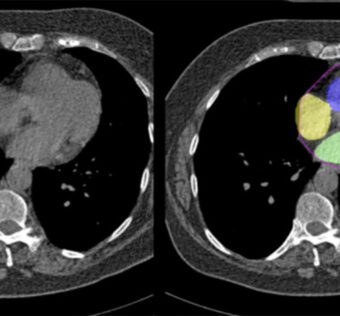

Cedars Sinai Researchers Uses AI to Analyze Regular Chest CT Scans to Predict Heart Disease RiskHIT Consultant - (Wednesday April 24, 2024) - AI/ Digital Health/ Frequent Updates/ HIT Consultant | |

![]() | What You Should Know: – Researchers at Cedars-Sinai have developed a new method using artificial intelligence (AI) to assess cardiovascular disease risk during a routine chest computed tomography (CT) scan without contrast dye. – The recent... #AIinHealthcare: Researchers at Cedars Sinai are utilizing artificial intelligence to analyze routine chest CT scans for predicting heart disease risk. The study aims to revolutionize cardiovascular risk assessment by leveraging advanced technology. #CedarsSinaiResearch #HeartDiseasePrediction#CTScanAnalysis: The use of AI in analyzing regular chest CT scans offers a non-invasive and efficient method for assessing heart disease risk. This innovative approach has the potential to enhance early detection and prevention strategies. #CardiovascularHealth #InnovativeTechnology#ResearchFindings: Preliminary results from the study indicate promising outcomes in accurately predicting heart disease risk based on chest CT scan analysis. The integration of AI into healthcare workflows could significantly impact patient care and outcomes. As a healthcare IT expert, write a 50-80 extractive summarization summary for social media platforms, that is focused, accurate, and strictly reflects the content based on a blog post from the given URL. The summary should include all headings from the blog post, with inline hashtags for each heading. When including the inline hashtags, use specific hashtags related to the headings rather than generic healthcare or technology hashtags. If the headings in the blog post are too long or unclear, feel free to rephrase them into shorter, clearer versions that still convey the main idea. The target audience is other healthcare IT professionals.Following is the title and url. Cedars Sinai Researchers Uses AI to Analyze Regular Chest CT Scans to Predict Heart Disease Risk https://hitconsultant.net/2024/04/24/ai-can-now-analyze-regular-chest-ct-scans-to-predict-heart-disease-risk/ { "id": "chatcmpl-9HhkwUYH9sYh3Y8HUaV7SufqInBtw", "object": "chat.completion", "created": 1714006802, "model": "gpt-3.5-turbo-0125", "choices": [ { "index": 0, "message": { "role": "assistant", "content": "#AIinHealthcare: Researchers at Cedars Sinai are utilizing artificial intelligence to analyze routine chest CT scans for predicting heart disease risk. The study aims to revolutionize cardiovascular risk assessment by leveraging advanced technology. #CedarsSinaiResearch #HeartDiseasePredictionnn#CTScanAnalysis: The use of AI in analyzing regular chest CT scans offers a non-invasive and efficient method for assessing heart disease risk. This innovative approach has the potential to enhance early detection and prevention strategies. #CardiovascularHealth #InnovativeTechnologynn#ResearchFindings: Preliminary results from the study indicate promising outcomes in accurately predicting heart disease risk based on chest CT scan analysis. The integration of AI into healthcare workflows could significantly impact patient care and outcomes." }, "logprobs": null, "finish_reason": "length" } ], "usage": { "prompt_tokens": 191, "completion_tokens": 150, "total_tokens": 341 }, "system_fingerprint": "fp_c2295e73ad" } Prompt Tokens - 191 |